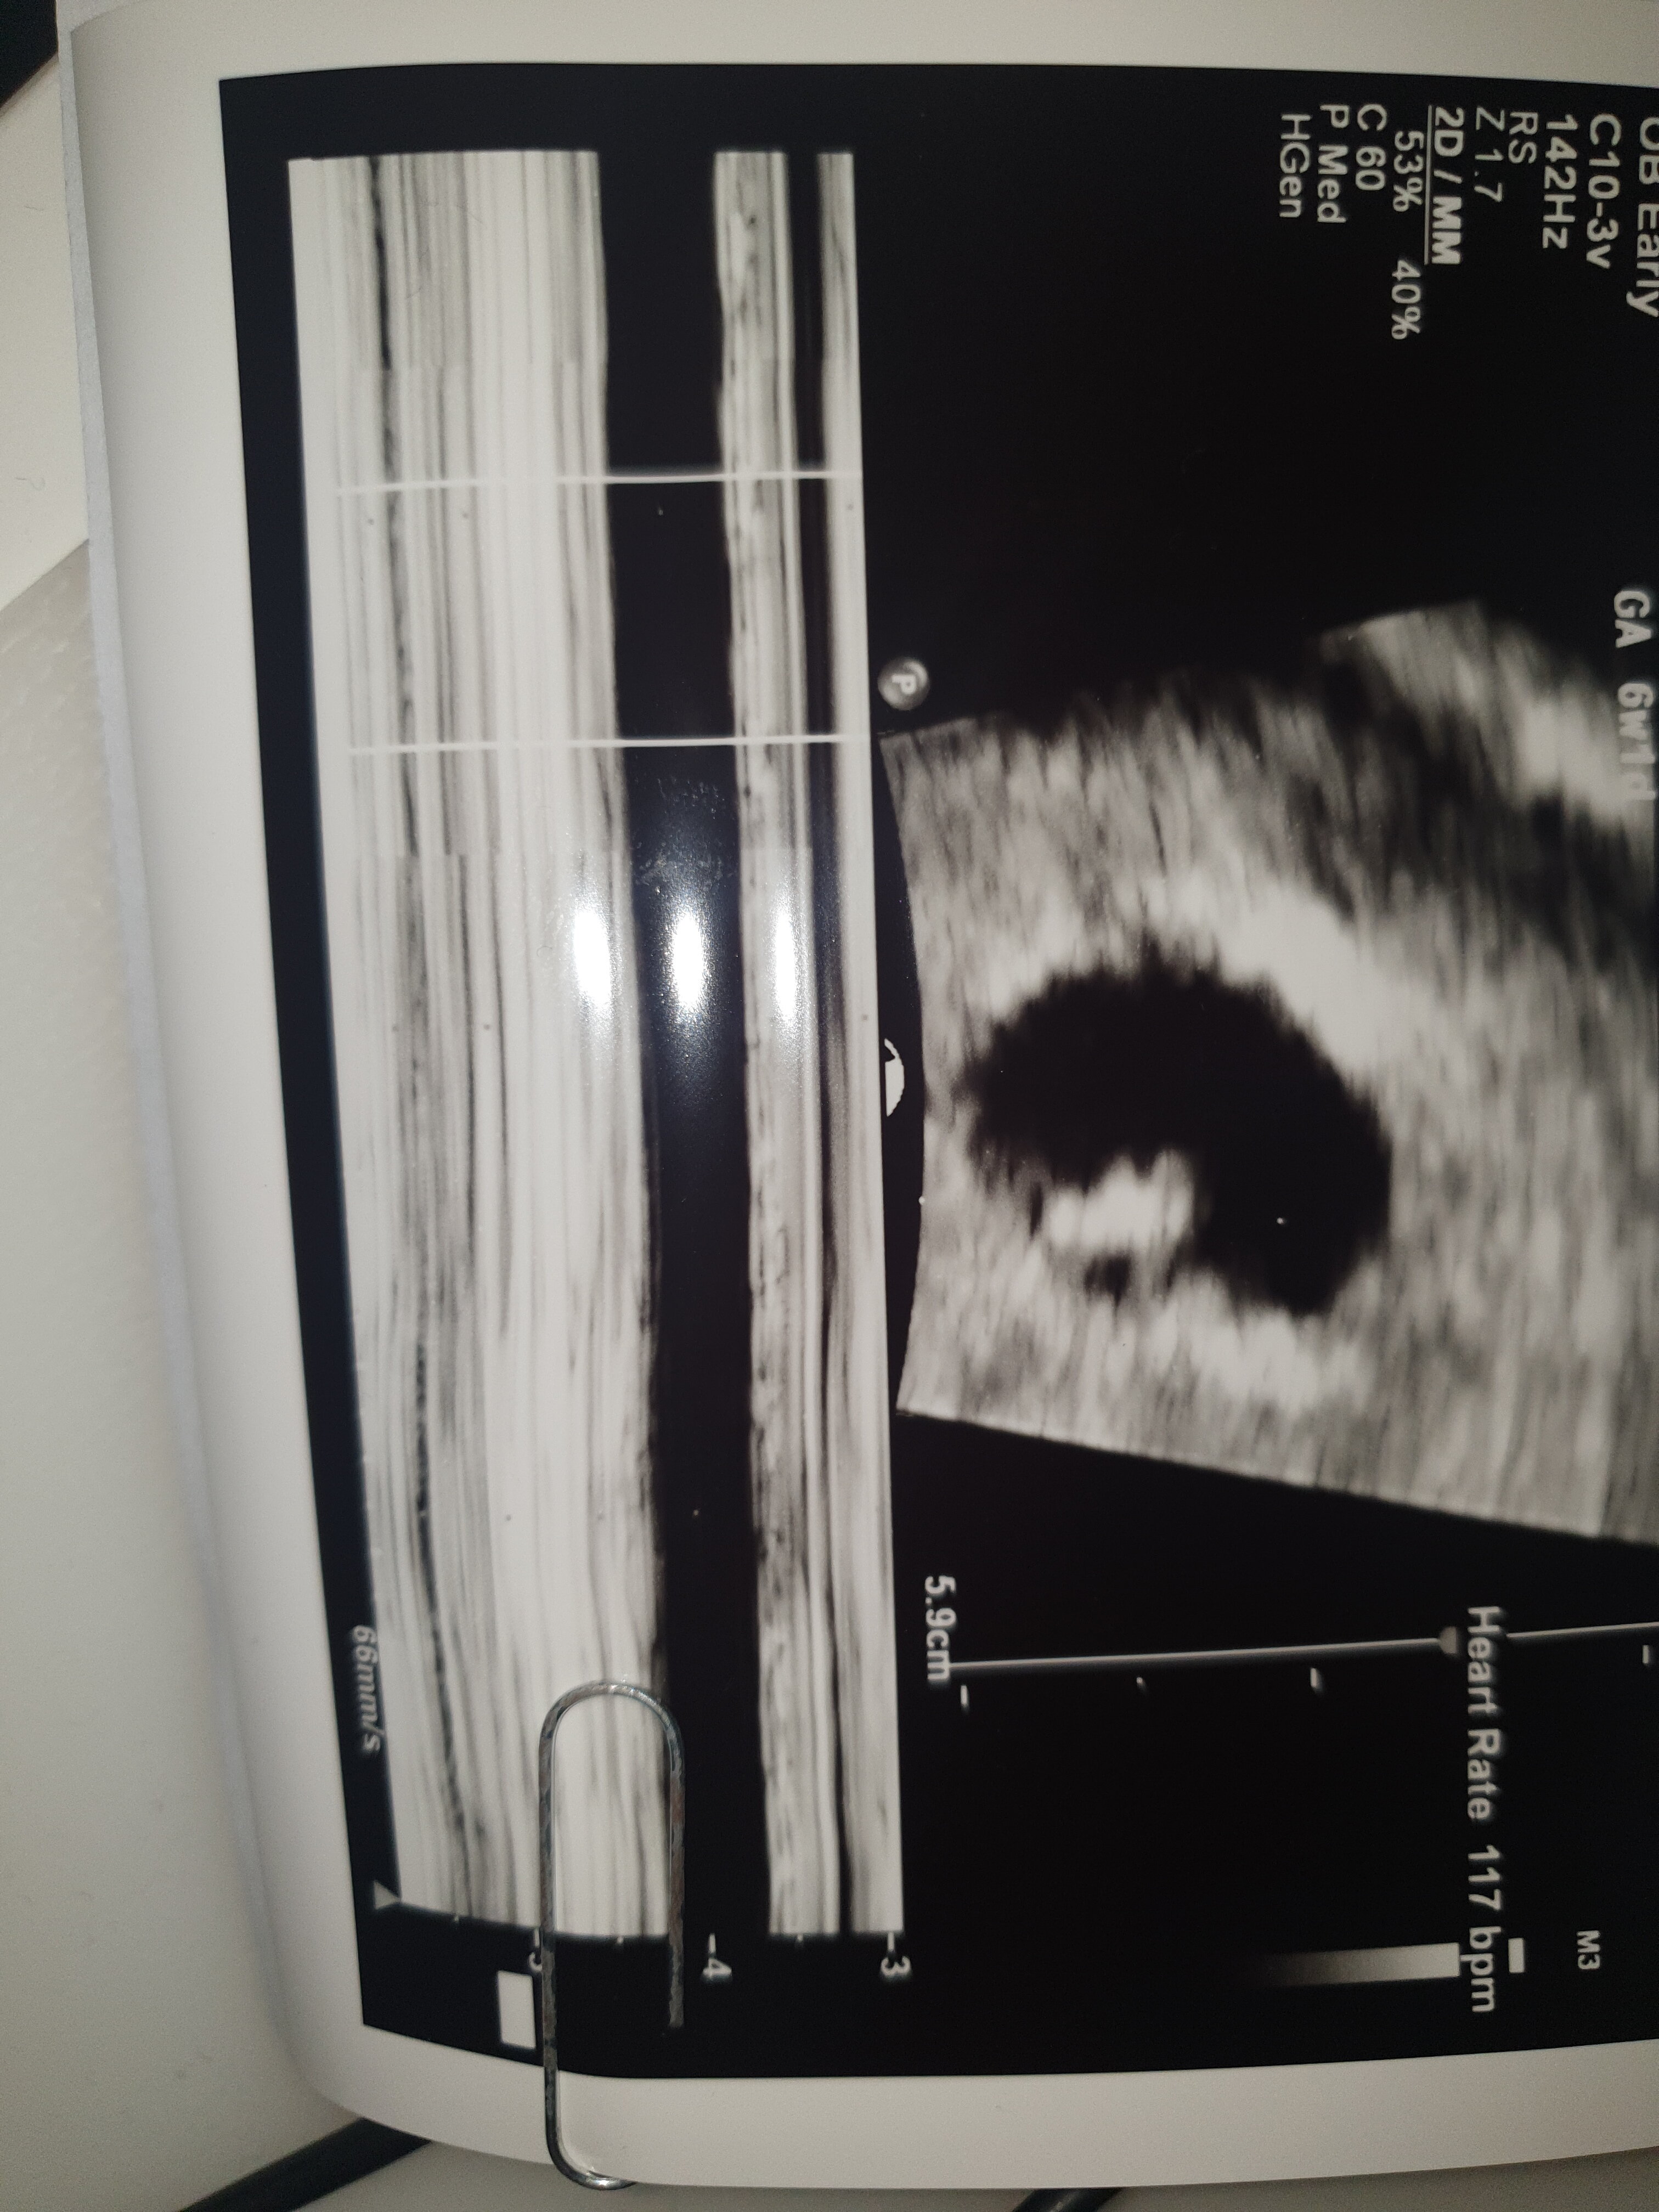

No ja ci powiem że okres miałam 12.01, byłam wczoraj na wizycie też wychodziło mi 7+1, ale ciąża młodsza 6+4 jednak zarodek i serduszko już jest [emoji4], czyli jeśli miałaś regularne okresy to jest duża szansa że już będzieMam wizytę 16.03 ale nie wiem czy wytrzymam tak długo żeby zobaczyć czy wszystko gra.. siedzę w domu i wariuje przez te negatywne myśli i przeświadczenie że to jakiś sen i się obudzę. :/ ostatni poczatek okresu miałam 15.01 myślicie ze w przyszłym tygodniu widać byłoby juz serduszko? Wg kalendarza ciąży byłoby 7+1..

Ja mam om 14.01, na wizycie bylam 01.03 i było już serduszkoMam wizytę 16.03 ale nie wiem czy wytrzymam tak długo żeby zobaczyć czy wszystko gra.. siedzę w domu i wariuje przez te negatywne myśli i przeświadczenie że to jakiś sen i się obudzę. :/ ostatni poczatek okresu miałam 15.01 myślicie ze w przyszłym tygodniu widać byłoby juz serduszko? Wg kalendarza ciąży byłoby 7+1..

Ja miałam om 13.01 a usg 2 marca i też było serduchoJa mam om 14.01, na wizycie bylam 01.03 i było już serduszko![]()